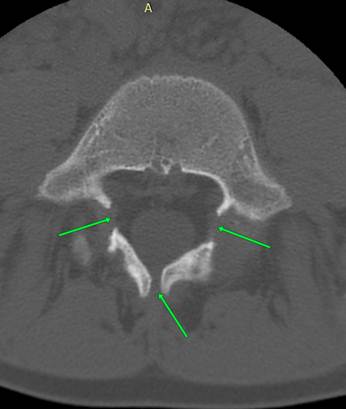

позвонка и его spina bifida. Выполнена РК - томография пояснично – крестцового сочлениения,

обнаружившая значительное недоразвитие дуги пятого поясничного позвонка с

широкими разрывами в межотростчатой зоне, пластинка дуги состоит из двух

костных фрагментов неправильной формы, spina bifida, остистый

отросток отсутствует. Диагноз: диспластический спондилолистез L5 1 степени. Назначены строгий постельный режим,

КТ

– эмуляция рентгенограммы и снимок с КТ – томограммы вышеописанного больного.

позвонка (1 степень по Меердингу). Угол Митбрейта 53° - значительно увеличен. На аксиальном скане 5

поясничного позвонка видно нарушение развития его дуги: справа и слева имеют

место широкие просветы в межотростчатых зонах, они обозначены стрелками.

Имеется Spina Bifida,

также обозначена стрелкой.